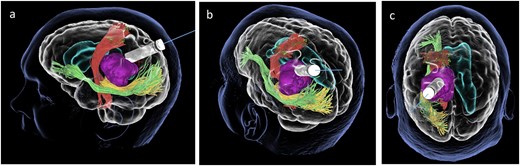

Lateral (a), ¾ lateral (b), and posterior (c) views of the pre-operative virtual 3D reconstruction model. The tumour (purple) is reached by the tubular retractor (white) and encircled by the associated white matter tracts: the CST (red) superiorly and anteriorly, and the IFOF (green) and the OR (yellow) that are located inferiorly, laterally, and posteriorly to the lesion.